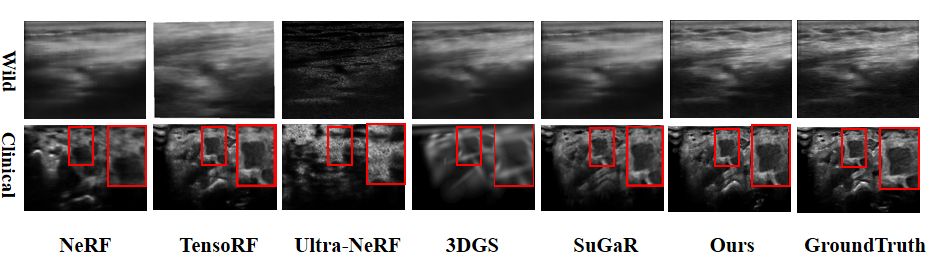

Figure 3: A visual reconstruction comparison on Wild Dataset and Clinical Dataset.

The visual comparisons in Fig. 3 and Fig. 4 provide additional evidence of these advantages. NeRF and Ultra-NeRF reconstructions are heavily degraded by noise and blurring artifacts, while 3DGS reconstructions exhibit noticeable structural misalignments. TensoRF and SuGaR generate sharper details but lack robustness across datasets, leading to inconsistent visual quality. In contrast, UltraGS produces reconstructions that better preserve anatomical boundaries, maintain sharper edge details, and achieve higher contrast, which are closer to the ground truth. This consistency across datasets and clinical cases underscores UltraGS’s effectiveness in capturing complex tissue structures while suppressing noise. More visual results can be found in the supplementary materials.

Table 1 presents a quantitative comparison between UltraGS and other methods, on both the Wild and Phantom datasets. Across all evaluation metrics, UltraGS achieves the best performance. Specifically, it consistently obtains the highest PSNR and SSIM values, while simultaneously delivering the lowest MSE, which highlights its superior reconstruction accuracy and image fidelity. Beyond quality, UltraGS also demonstrates exceptional computational efficiency, achieving 64.69 fps, which is more than an order of magnitude faster than most NeRF-based methods. These results collectively confirm UltraGS’s capability to provide both accurate and efficient novel view synthesis in ultrasound imaging.

Performance on the Clinical Dataset is further summarized in Table 2, where UltraGS consistently outperforms competing methods across all six cases. While NeRF and Ultra-NeRF often suffer from blurred reconstructions with high noise, and 3DGS produces misaligned structures, our method maintains stable improvements in both PSNR and SSIM across diverse patient cases. Even compared with TensoRF and SuGaR, which show partial improvements in specific scenarios, UltraGS achieves more reliable results overall, indicating its strong adaptability to different clinical conditions.